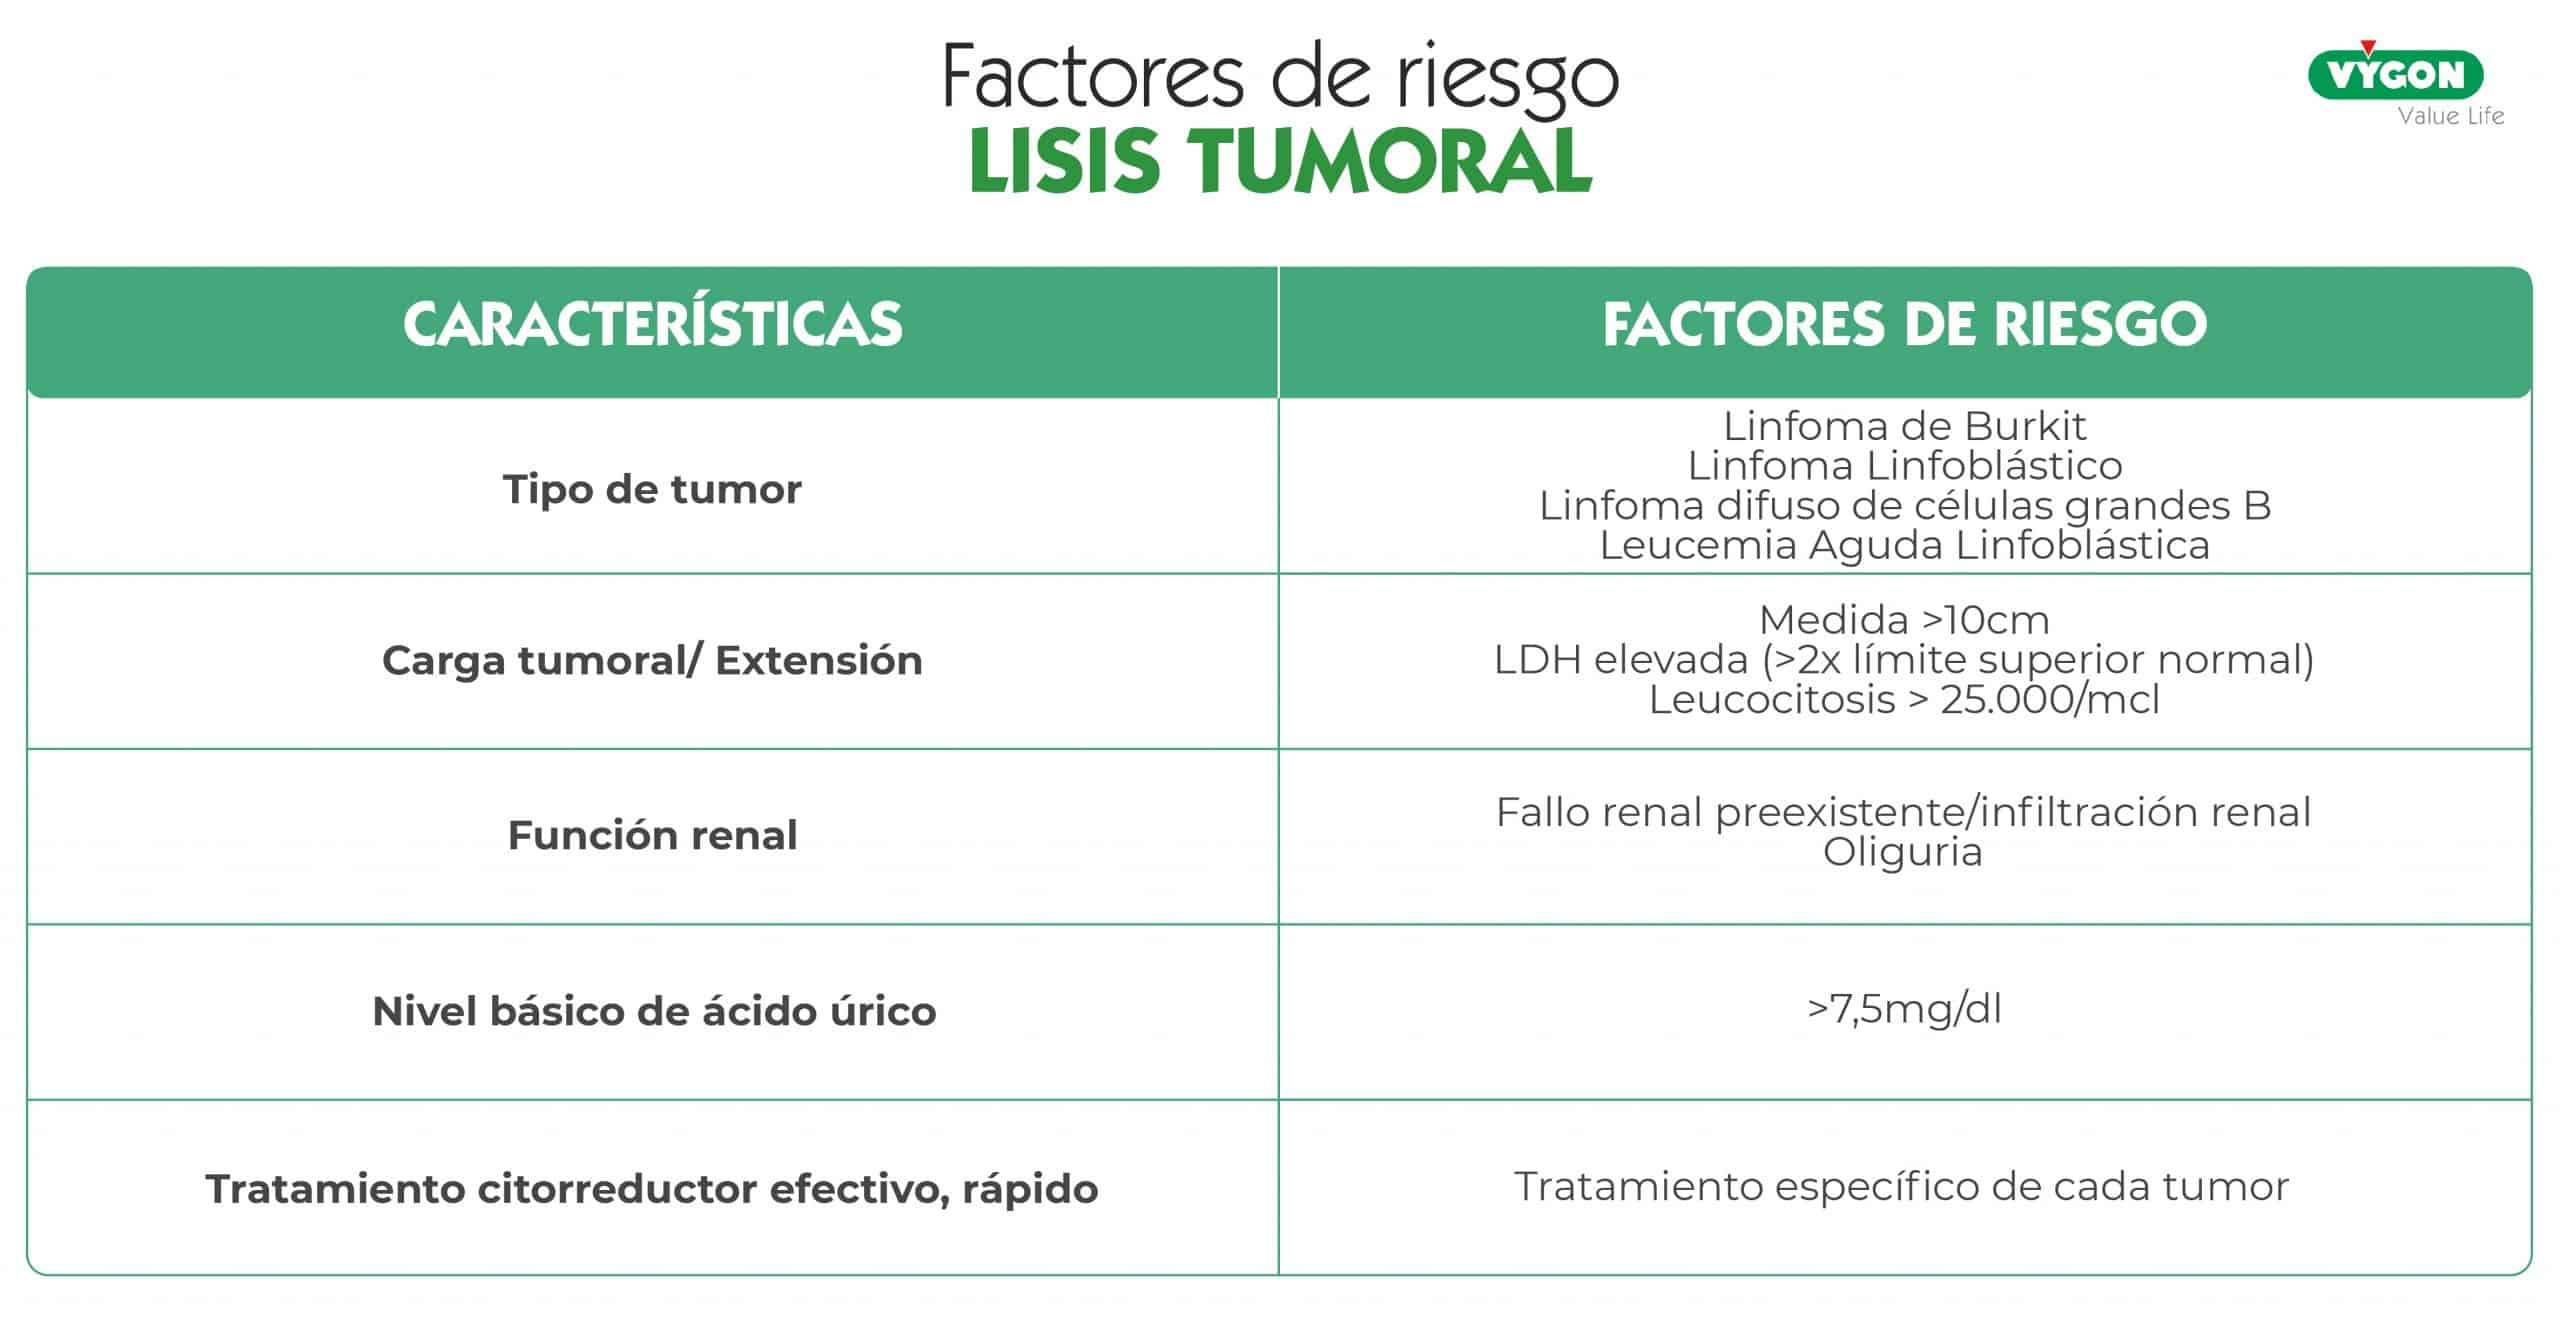

Factores de riesgo

Existen una serie de factores que aumentan la probabilidad de sufrir una lisis tumoral y que dependerán de:

Tipo de tumor.

- Linfoma de Burkit.

- Linfoma Linfoblástico

- Linfoma difuso de Células grandes B Leucemia Aguda Linfoblástica

- Tumor sólido con elevada proliferación

Carga tumoral/extensión.

- Medida >10cm.

- LDH elevada (>2x límite superior normal).

- Leucocitosis > 25.000/mcl

Función renal

- Fallo renal preexistente/infiltración renal

- Oliguria

Nivel básico de ácido úrico

- >7,5mg/dl

Tratamiento citorreductor efectivo, rápido

- Tratamiento específico de cada tumor